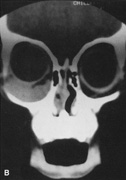

Fig. 16. A. Patient with right orbital cellulitis. B. Coronal CT scan demonstrating subperiosteal abscess formation from frontal and ethmoidal sinusitis. C. Frontoethmoidal orbitotomy incision marked for abscess drainage.

A frontoethmoidal, or Lynch, skin incision is marked halfway between the medial canthus and bridge of the nose. It extends superiorly and inferiorly in a curved fashion approximately 2 to 3 cm (Fig. 16). The exact limits of the incision depend on the location of the underlying lesion. Injection of local anesthetic with epinephrine provides vasoconstriction, which greatly enhances hemostasis. After the skin is incised, a unipolar cutting cautery is used to extend the incision deeply to the periosteum. Bleeding may be encountered, especially in the area of the angular artery and vein. Exposure is enhanced with 4-0 silk sutures passed into the orbicularis muscle and clamped to the drapes.

The periosteum is exposed and incised with a Freer elevator and then is reflected off the bone posteriorly. It is generally quite adherent to the curved contour of the medial canthal bones, especially at the medial canthal tendon. The anterior lacrimal crest is encountered inferiorly. Care should be taken not to damage the lacrimal sac with the elevator. The posterior lacrimal crest is visible behind the sac. Adequate mobilization of the periosteal connections to the anterior lacrimal crest gives a large area of exposure. The periosteal elevation is carried superiorly in the area of the trochlea. Elevation of the periosteum opens the subperiosteal space. Blood or pus caused by fracture or infection, if present in this space, is encountered at this point.